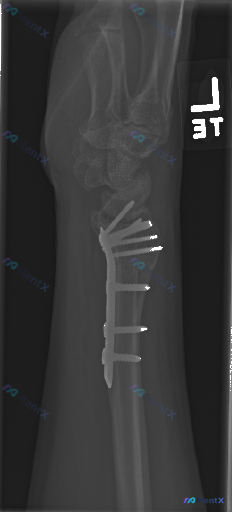

整理到一份左侧桡骨远端骨折术后的影像资料,大家一起讨论看看后续关注点应该放在哪里。 基本背景 左侧桡骨远端骨折,已行掌侧锁定加压钢板+螺钉内固定术。 本次影像(侧位X光)核心所见 1. 内固定:钢板位于桡骨远端掌侧,多枚螺钉在位,位置良好,未见明显松动、断裂或移位;螺钉末端在关节面下方,未明显进入关...